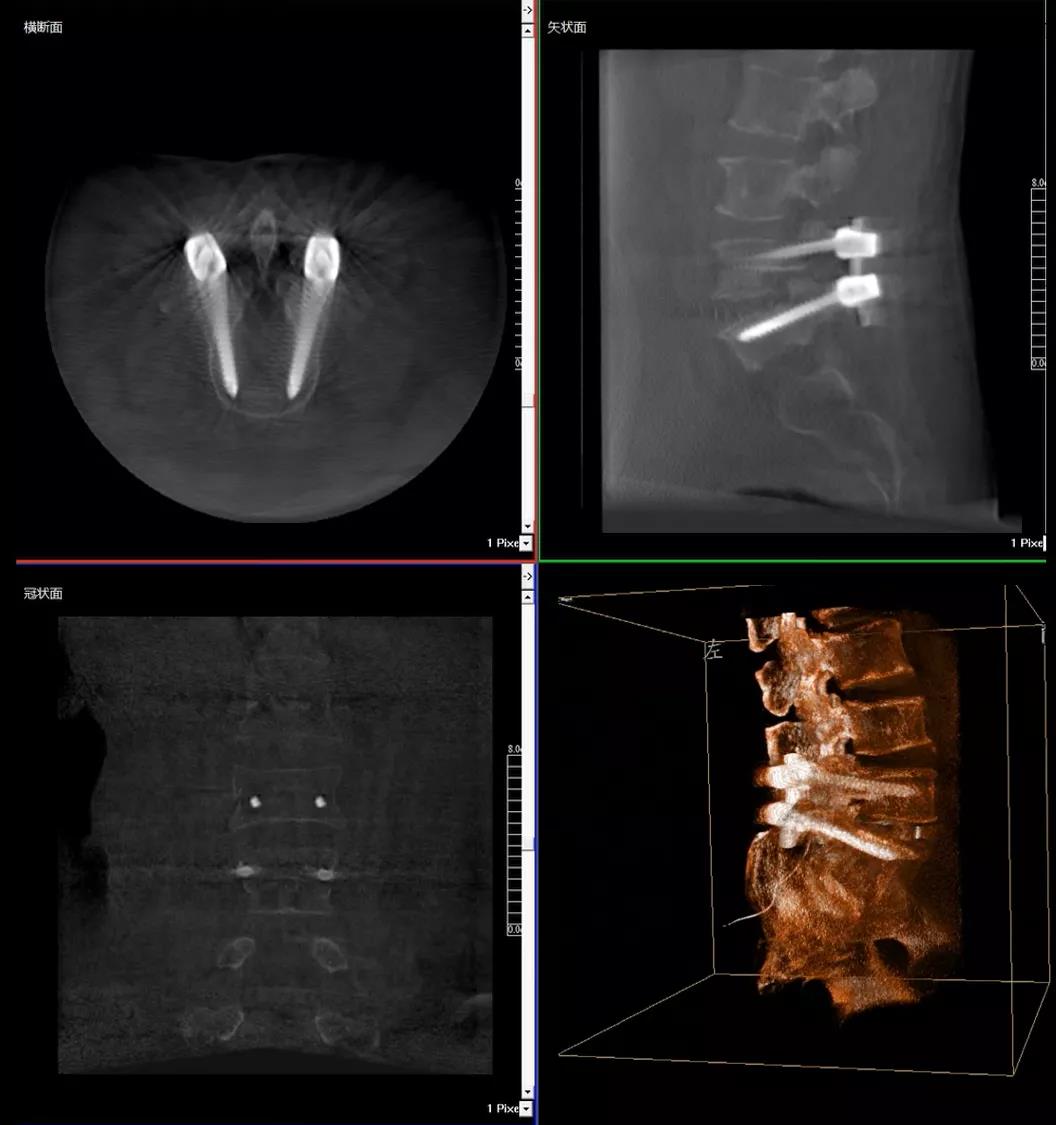

3D C形臂擺位及手術(shù)前二維影像

醫(yī)生在影像引導(dǎo)下在L5/S1椎弓根處打入醫(yī)用螺釘

術(shù)中快速生成橫斷面、矢狀面、冠狀面斷層圖像和三維立體圖像